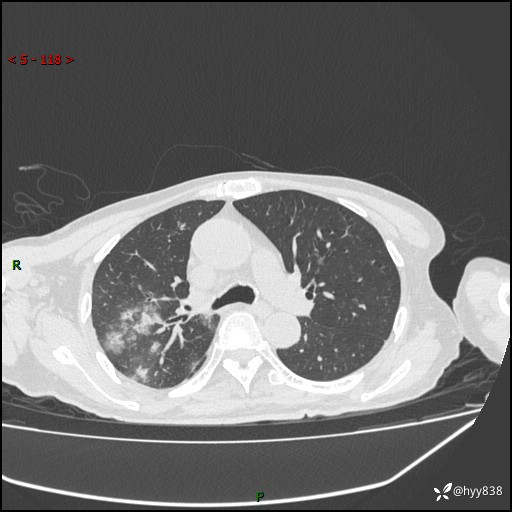

一个月后第二次CT检查(常规抗感染,患者不配合:增强、住院---)